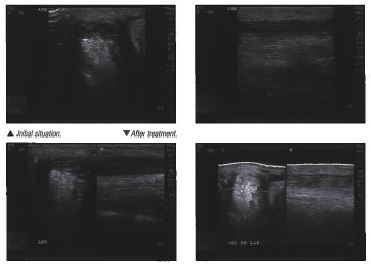

MLS® Laser Therapy

Light-Based Pain Management

The patented MLS system is a unique Class IV laser that synchronizes continuous and pulsed emission to provide unparalleled clinical results without generating heat.

With device configurations that offer stress-free, no-touch protocols, MLS Laser Therapy is quickly becoming the standard of care for equine pain management.

- Tendon and Ligament Injuries